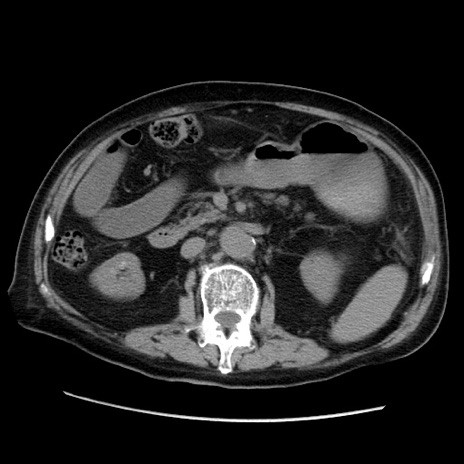

冠状断像

【症例】70歳代男性

【主訴】腹痛

【現病歴】肝硬変・肝細胞癌にてかかりつけの方。約9時間前に食後より腹痛出現。症状が徐々に増悪し、嘔吐出現したため来院。

【既往歴】肝硬変、肝細胞癌(RFA、TACE後)

【身体所見】意識清明、表情苦悶様、BT 36℃、BP 129/78mmHg、P 88bpm、SpO2 97%(RA)、右上腹部から心窩部にかけて圧痛あり、反跳痛なし、筋性防御あり。

【データ】WBC 5800、CRP 0.16